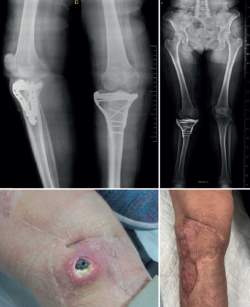

- Comorbilidades del paciente que contraindiquen fijación interna o influyan negativamente en procesos de cicatrización (diabetes, tabaquismo, mal estado basal) (Figura 3).

Figura 3. Fractura de grado VI de Schatzker con mal estado de las partes blandas en paciente diabético. Se decidió tratamiento definitivo con fijación externa circular en hexápodo.